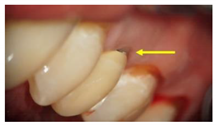

GroupDescription Clinical Presentation

Group-I (n = 35)Received a conventionally fabricated cobalt-chrome (Co-Cr) ceramic prosthesis; conventional wax up copings were converted to metal copings by the lost wax technique followed by porcelain layering.Molecules 26 01331 i001

Arrows show the crown margins and gingival tissues interface.